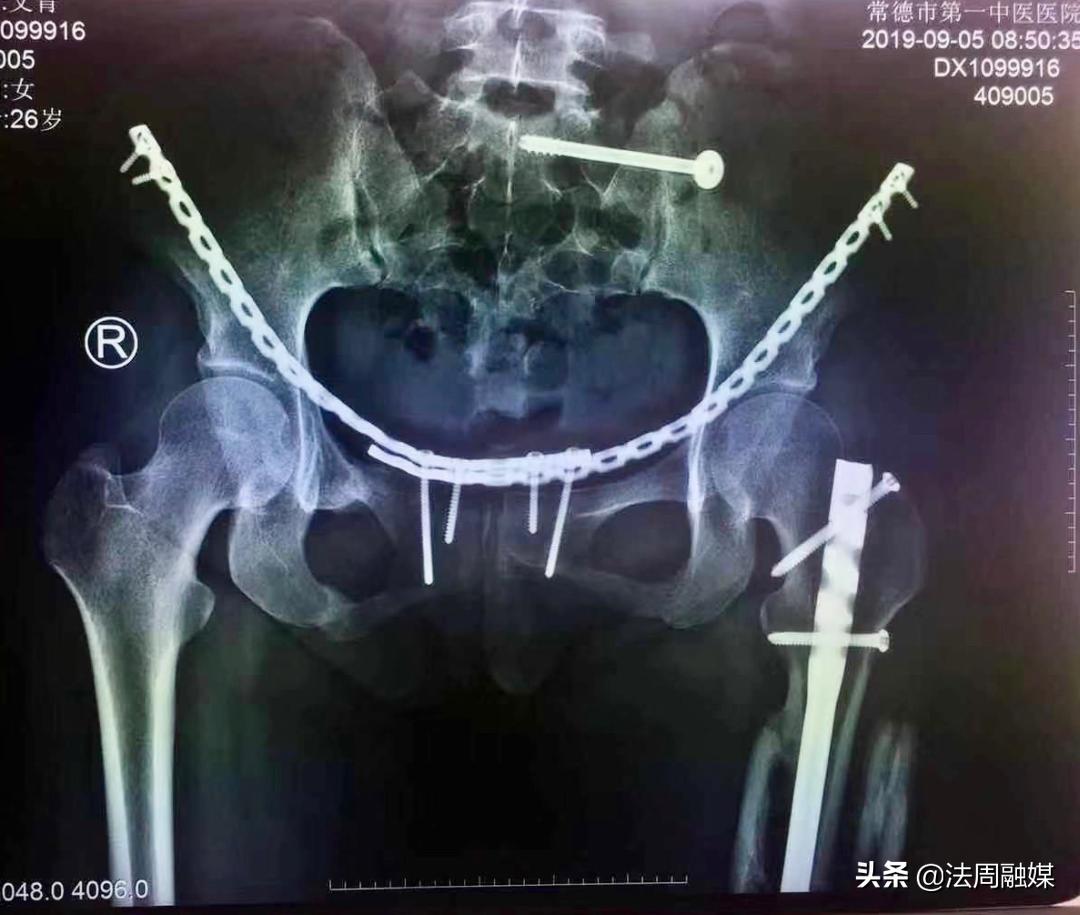

当时,小文被120救护车紧急送往常德市第一中医医院,骨伤科创伤病区副主任医师肖群飞接诊后,紧急予以左小腿彻底清创,外固定支架固定,抗生素骨水泥植入+VSD覆盖术。住进ICU后,在重症监护室医护人员精心治疗下,小文的生命体征平稳,各方面情况趋于稳定,肖群飞予以骨盆钢板螺钉内固定术、股骨干闭合复位髓内钉内固定术,伤口逐渐愈合,身心创伤也逐渐褪去,重拾生活信心。

由于损伤严重,骨缺损,小文在后期康复中,骨折部位愈合不良并出现“马蹄内翻足”,站立行走困难。此时,肖群飞想出了奇招,去除外固定架,闭合扩髓达到植骨目的并髓内钉固定促进骨折愈合,再利用“克氏针配合橡皮筋”持续牵引纠正马蹄足内翻。后来,经过医生的精准治疗和自身不断的康复锻炼,小文逐渐站立起来,筑立起了明日美好的生活!